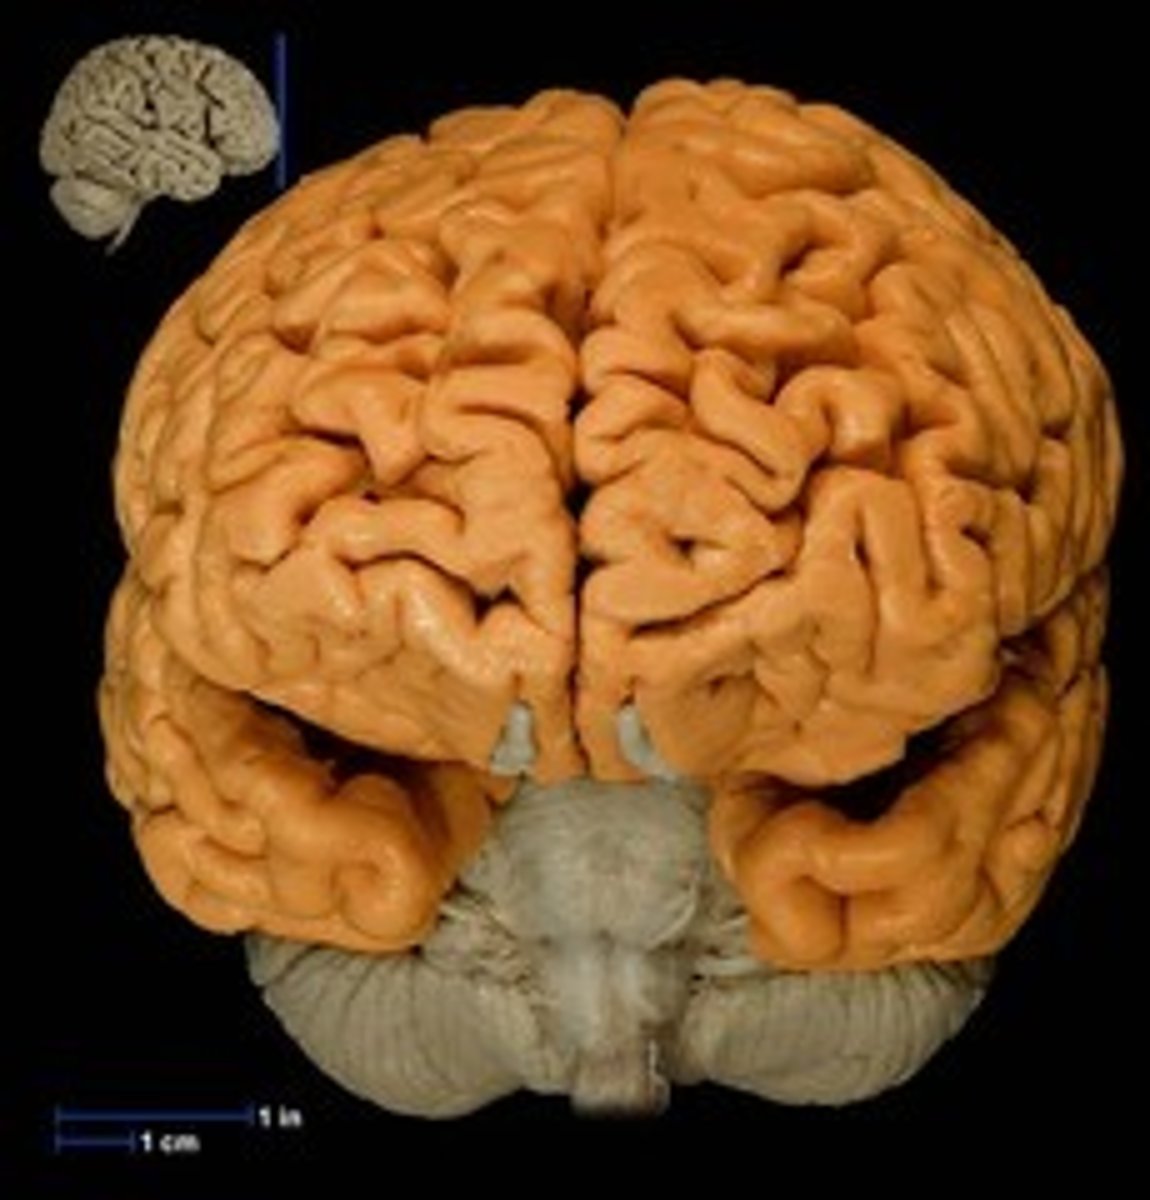

Cerebrum

"the whole brain;" The largest division of the brain. It is divided into two hemispheres, each of which is divided into four lobes.

cerebral cortex

the intricate fabric of interconnected neural cells covering the cerebral hemispheres; the body's ultimate control and information-processing center.